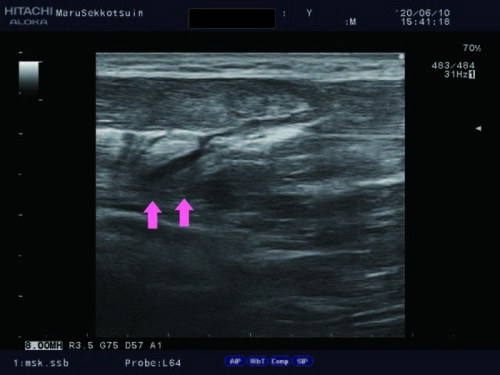

足を捻って「第四中足骨骨折」

第4中足骨骨折.jpg